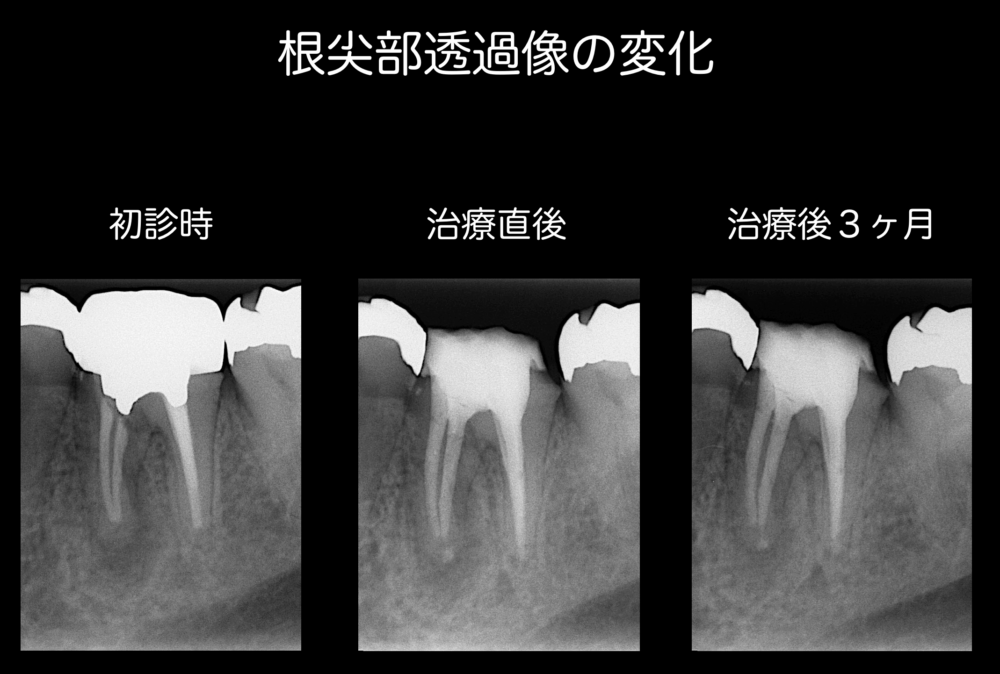

根管治療終了直後と術後3ヶ月経過観察時のレントゲンです。

近心根の根尖部透過像は縮小傾向にあります。